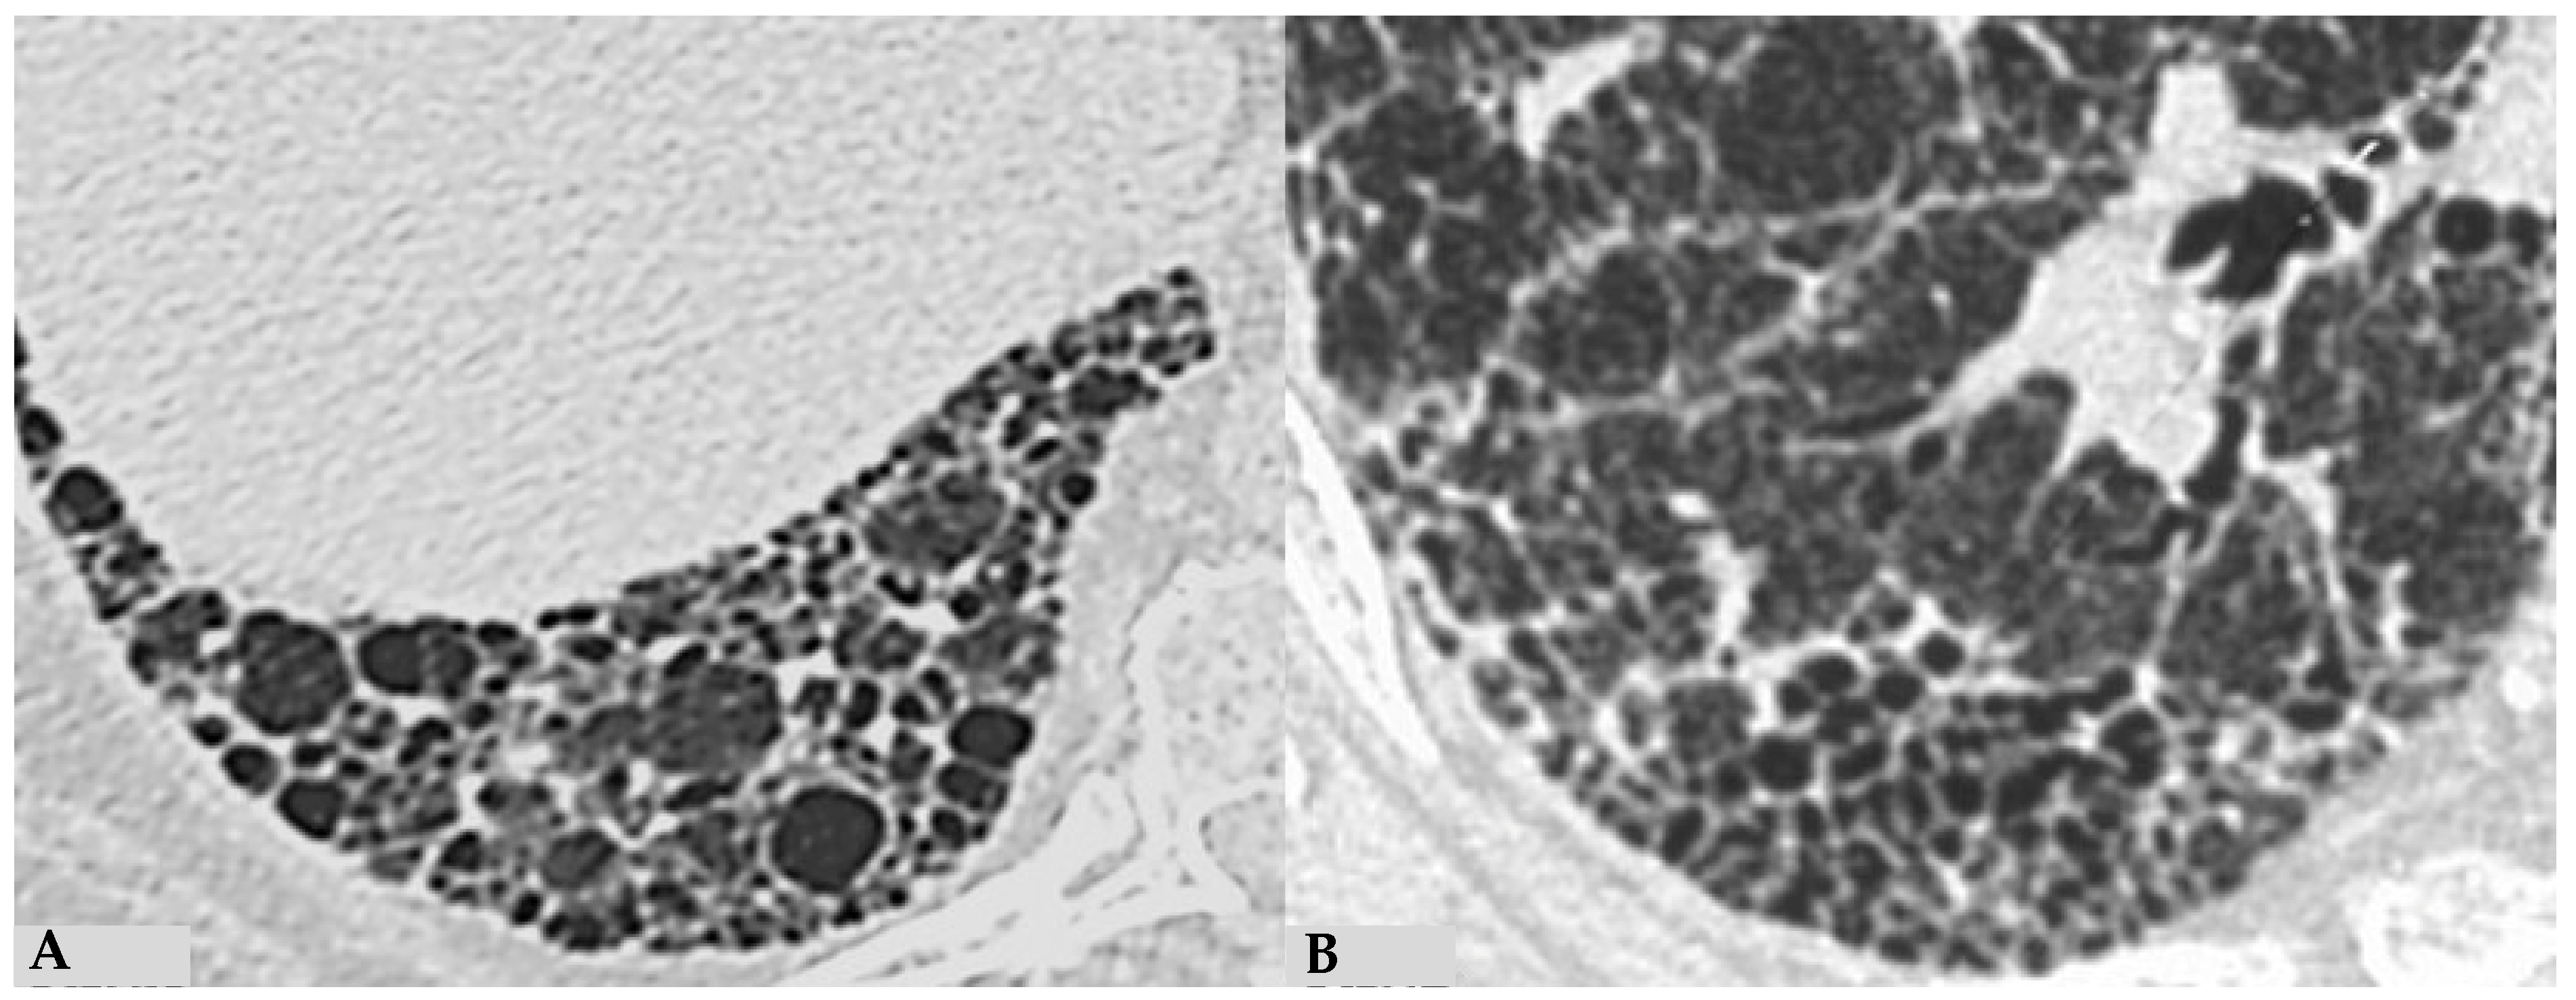

4. Pathologic Features of Fibrotic Hypersensitivity Pneumonitis

The insidious fibrotic counterpart of HP poses a diagnostic challenge in the ILD scenario from clinical, radiological and purely pathological perspectives. Diagnostic complexities arise partly from the myriad findings discernible in FHP, the divergences regarding defining characteristics of FHP and the chameleon-like nature of FHP to mimic other forms of fibrotic ILDs, particularly UIP/IPF. International guidelines advise against biopsy in clinically and radiologically defined UIP pattern cases. Biopsies are typically reserved for atypical/indeterminate forms. Importantly, a significant proportion of surgical and cryobiopsies in fibrotic ILD contexts correlate with FHP. Distinguishing fibrotic HP from UIP/IPF is not merely an academic exercise, as treatments significantly differ, especially since advanced forms of HP, exhibiting progressive features, do not benefit from corticosteroid treatment but may benefit from antifibrotic therapy. Fibrotic alterations in HP manifest in various forms: bronchiole-centric fibrosis, typically subpleural fibrosis, an NSIP-like fibrotic form and a UIP-like form. Granulomas and giant cells in FHP resemble those in non-HP but, unlike the latter, may exhibit ubiquitous distribution in lung parenchyma rather than being confined to peribronchiolar anatomy. A crucial pathological aspect concerning fibrosis in the evolving framework of HP is the classical “bridging fibrosis” appearance of peribronchiolar metaplasia, typically “air-centered” and better known as “bridging fibrosis”. This feature is generally a reliable pathological marker of FHP, usually affecting a substantial number of bronchioles (>50%). However, occasional foci of peribronchiolar metaplasia may be found in any fibrotic interstitial pneumonia and even in otherwise normal lungs. Therefore, determining the proportion of affected bronchioles is necessary for using this characteristic in FHP diagnosis. Granulomas and giant cells are valuable when present, as are infiltrates and lymphocyte aggregates; however, they are found only in a minority of FHP cases (Figure 11). “End-stage lung” findings with honeycombing indicate a UIP pattern, necessitating correlation with historical, clinical, functional and radiological data, and sometimes pathological data, to provide conclusive information about a specific disease, as isolated findings only signify progressive and final fibrotic damage (Figure 12A). Granulomas/giant cells are similar to those found in NFHP, but unlike the latter, they can be found anywhere in the parenchyma and not just in a peribronchiolar position. Moreover, they are highly useful when present; however, they are found only in a minority of FHP cases. In the differential diagnosis, granulomas and giant cells can occasionally be found in CTD-ILDs or even in other non-necrotizing chronic granulomatous diseases such as sarcoidosis but are not part of pathological alterations seen in UIP/IPF forms [17,18,19]. As in NFHP, Schaumann bodies are occasionally present and serve as substitutes for granulomas (Figure 12B). The interstitial inflammatory infiltrate of FHP may be scanty, as in UIP/IPF, or moderately “cellular,” primarily composed of lymphocytes with a variable number of plasma cells and occasionally some eosinophils when present. Foci of fibroblasts are common in FHP and potentially analogous in pathological configuration to those found in idiopathic forms (UIP/IPF), although often numerically fewer than in idiopathic pathologies such as IPF, and may be associated with isolated peribronchiolar fibrosis. It has also been postulated that fibroblast foci associated with peribronchiolar fibrosis reliably point towards a diagnosis of FHP rather than UIP/IPF diagnosis [20,21]. The differential diagnosis of FHP includes some chronic evolution forms of sarcoidosis, aspiration pneumonitis, collagenopathy-related ILDs, some forms of NSIP and even some clinical-radiological and pathological forms of Interstitial Pneumonia with Autoimmune Features (IPAF). In any case, it is crucial to emphasize that the diagnosis of each ILD is an integrated multidisciplinary process, where each piece must be precisely analyzed by dedicated specialists (pulmonologist, radiologist, pathologist, rheumatologist). Only through the correct interaction of the MDT elements can a coherent and sometimes conclusive diagnosis be achieved.

Figure 11.

FHP: diffuse fibrotic change with lymphocytic infiltration and giant cells ((A): hem-eo 20×); FHP with predominantly airway-centered inflammation characterized by peribronchiolar metaplasia, foamy macrophages in alveolar spaces, poorly formed granulomas and giant cells ((B): hem-eo 40×).